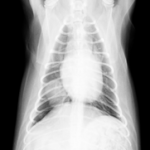

症例:10歳 チワワ 避妊雌

主訴:最近咳をたびたびしており、他の病院にてレントゲン検査をしたところ肺の右後葉に腫瘍が認められたため、手術のため当病院を紹介されて来院されました。

当病院のレントゲン検査でも肺腫瘍が認められたため、咳の症状も腫瘍によるものと診断、飼い主様の希望により肺腫瘍摘出手術を行いました。